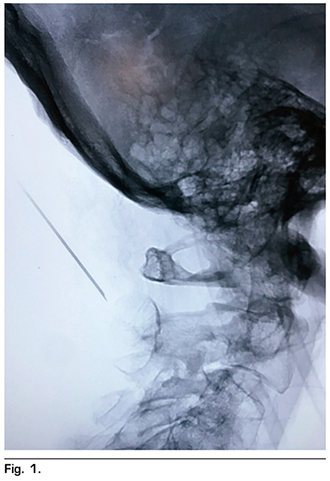

La técnica que se utilizó fue descrita por Racz y cols. (12), se localizaron mediante guía fluoroscópica a través de un arco C y en una posición anteroposterior las vértebras cervicales 1 y 2, posteriormente se rotó el equipo de arco en C a 90° para observar una proyección lateral, localizando las apófisis espinosas de las vértebras cervicales 1 y 2 (C-1 y C-2). Se eligió el punto de abordaje, localizado a 2 centímetros lateral izquierda de la protuberancia occipital mayor en la línea nucal superior, se infiltró piel cabelluda y tejido celular subcutáneo con lidocaína simple al 2 %. Posteriormente se introdujo una aguja espinal BD tipo Quincke 22 G 88 mm, en sentido cefalocaudal y lateromedial; de manera cuidadosa se avanzó a través de las capas fasciales musculares para evitar una lesión nerviosa o vascular (entre las que se encuentran la raíz nerviosa de C-1 o nervio suboccipital, raíz nerviosa de C-2 o tercer nervio occipital, el plexo cervical, la arteria cervical ascedente, la arteria o vena cervical profunda, y la arteria o vena vertebral) hasta hacer contacto con apófisis espinosa de C-2 (Figura 1); se retiró 2 mm y se aspiró para verificar punción inadvertida de vasos o duramadre. Una vez confirmado que no hubo salida de sangre o líquido cefalorraquídeo, se administraron 4 ml de medio de contraste no iónico, observando una difusión hacia la región occipital de forma triangular (triángulo formado por los músculos oblicuo mayor, oblicuo menor, recto posterior de la cabeza y el semiespinoso de la cabeza) (Figura 2). Ya corroborado el objetivo terapéutico, se aspiró nuevamente y se administraron 5 ml de bupivacaína (25 mg) con metilprednisolona no soluble (40 mg) aforados en solución salina hasta un total de volumen de 10 ml en el lado afectado, observando una adecuada disección de los planos musculares antes descritos en la imagen fluoroscópica. Se retiró aguja, se pasó a la paciente a recuperación sin incidentes, ni complicaciones.